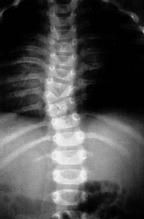

While the physical examination tips just described improve the sensitivity of detecting body asymmetries, they are not specific for scoliosis or precise for determining curve magnitude. These can be confirmed only by taking entire spine radiographs, both posteroanterior and lateral standing. The Cobb angle technique quantifies the amount of scoliosis, kyphosis, or lordosis1 (Figure 6). When describing scoliosis, note whether the curve is present in the cervical, thoracic, or lumbar spine and whether the apex of the curve is to the left or right. The most common finding in idiopathic scoliosis is a single right thoracic curve. A left thoracic curve is more ominous and suggests an underlying pathologic condition.

Also look at the iliac crests to make rough radiographic inferences about skeletal maturity (Figure 6 [right]). The iliac apophysis gradually fuses from anterolateral to posteromedial and is staged by the Risser system (Table 2). Progression takes about one year, and fusion an additional two years.2 Spinal growth is unlikely but can occur after fusion.3 Idiopathic curves are, therefore, less likely to increase in magnitude as the apophysis progresses. Bracing of idiopathic curves is recommended for curves between 20° and 40° in patients who are Risser 0, 1, or 2. Patients who are Risser 3 and above may not have enough growth remaining to benefit from bracing, but this is an individualized decision made by the orthopedic surgeon.